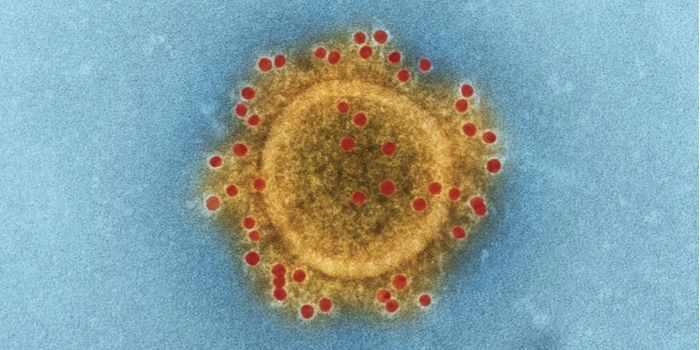

NOV 11, 2021MicrobiologyWhile many people are most familiar with the coronavirus that causes COVID-19, which is called SARS-CoV-2, there are man ...